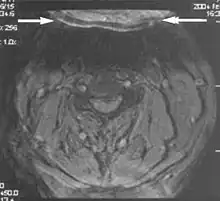

Metal artifacts occur at interfaces of tissues with different magnetic susceptibilities, which cause local magnetic fields to distort the external magnetic field. This distortion changes the precession frequency in the tissue leading to spatial mismapping of information. The degree of distortion depends on the type of metal (stainless steel having a greater distorting effect than titanium alloy), the type of interface (most striking effect at soft tissue-metal interfaces), pulse sequence and imaging parameters. Metal artifacts are caused by external ferromagnetics such as cobalt containing make-up, internal ferromagnetics such as surgical clips, spinal hardware and other orthopaedic devices, and in some cases, metallic objects swallowed by people with pica.[3] Manifestation of these artifacts is variable, including total signal loss, peripheral high signal and image distortion (Figs 3 and 4).[1] Reduction of these artifacts can be attempted by orientating the long axis of an implant or device parallel to the long axis of the external magnetic field, possible with mobile extremity imaging and an open magnet. Further methods used are choosing the appropriate frequency encoding direction, since metal artifacts are most pronounced in this direction, using smaller voxel sizes, fast imaging sequences, increased readout bandwidth and avoiding gradient-echo imaging when metal is present. A technique called MARS (metal artifact reduction sequence) applies an additional gradient, along the slice select gradient at the time the frequency encoding gradient is applied.